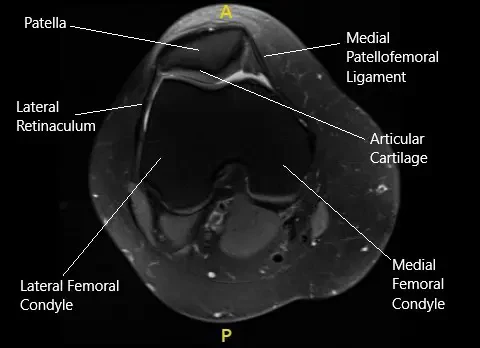

MRI of the right knee in axial section.

The MRI of the right knee suggested patellar mal-tracking. Due to the failure of the conservative management, the patient was advised surgical management. The risks, benefits, and potential complications were all discussed at length with the patient. The patient agreed to go ahead with the procedure.